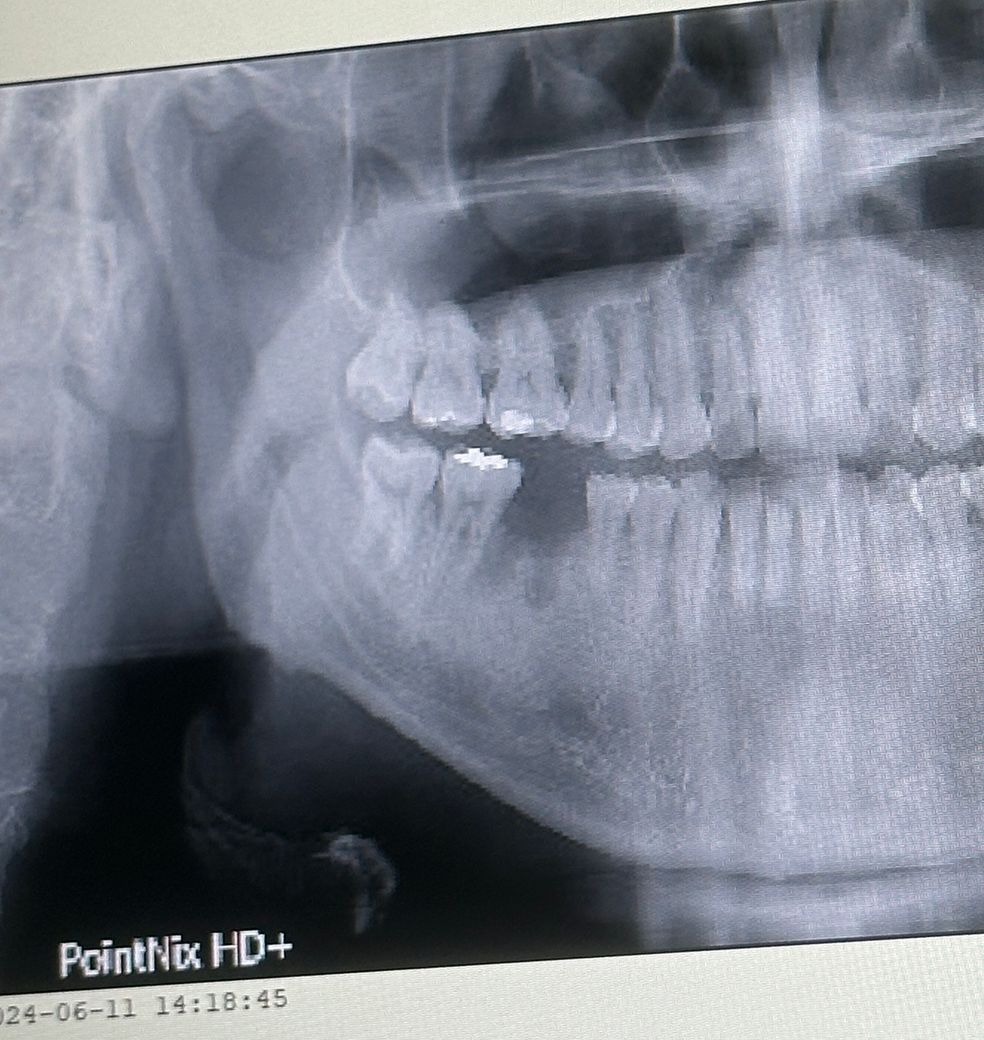

오늘 임플란트 수술+뼈이식 받았는데요

잘된걸까요? 다음3달이후에는 다시 수술할필요가앖이 바로 머리올린다고 하시네요

• 1번 째 사진

1. 임플란트 뿌리를 심은 후(1차 수술)에 임플란트 뿌리가 뼈에 붙을 때까지 뚜껑을 닫아두는데 두 종류가 있습니다. 그 중에 2차 수술을 진행하지 않아도 되는 타입(힐링 어버트먼트)을 달아둔 상태입니다. 3달 후 다시 수술할 필요가 없다는 것은 그걸 의미하고요.